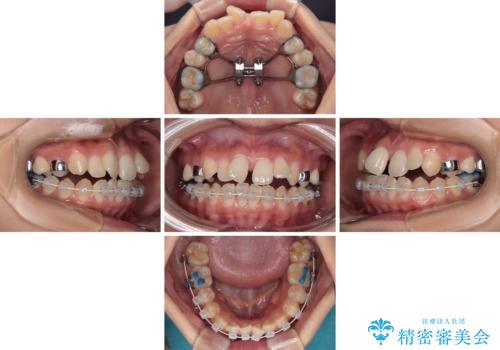

急速拡大装置 狭い骨幅を拡大した上で、口元の突出感を改善する抜歯矯正治療

単純に上下左右の第一小臼歯4本を抜歯して口元の突出感を改善することも考えられましたが、上顎骨よりも下顎骨の幅が広いため、より良い咬み合わせを達成することを目的として、急速拡大装置を用いて上顎骨を拡大することとしました。

歯列矯正では基本的に骨格を改善することはできませんが、急速拡大装置(MARPE)を使用することで上顎骨を側方に拡大させることができ、咬合状態を大きく改善することができます。